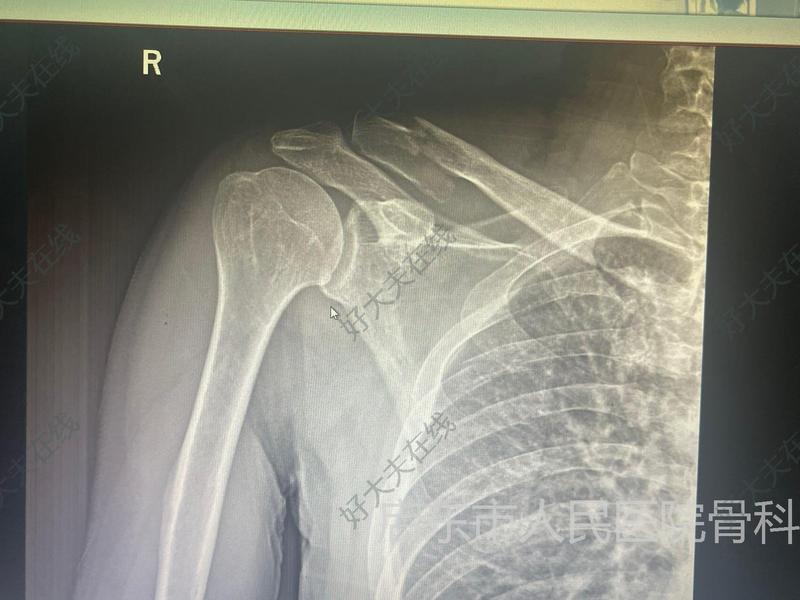

锁骨远端骨折

胡新锋医生的科普号

2023年03月30日